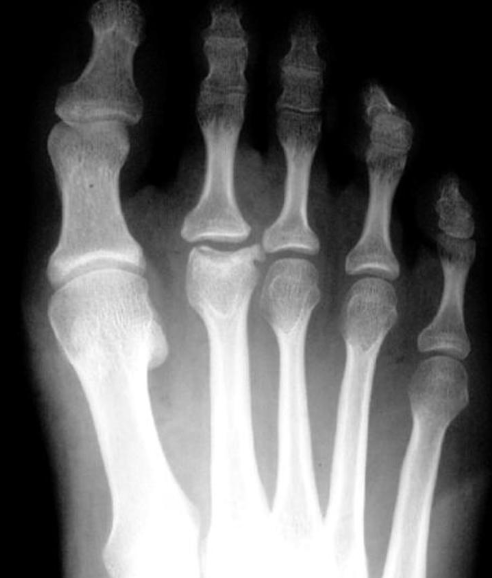

Fratura de Bennett

Fratura da base do primeiro metacarpo;

Intra-articular;

Dois fragmentos.